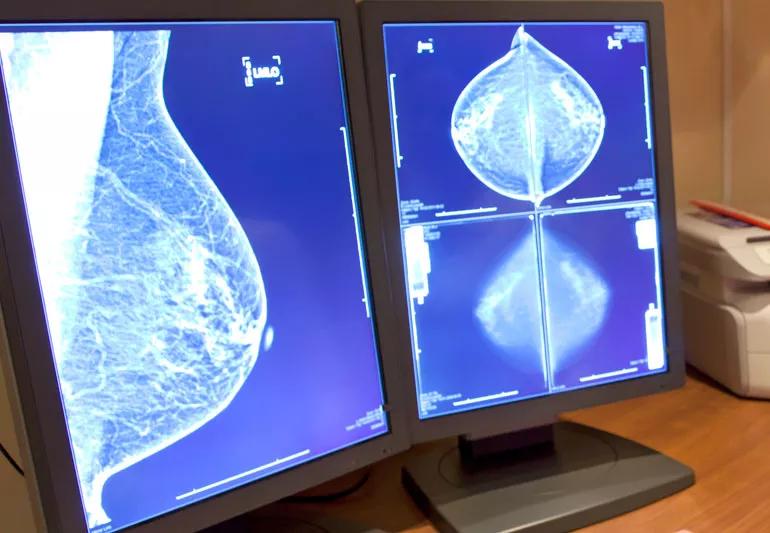

Mammography images on computer screens

“We saw something on your mammogram and want to check it out.” The words every woman dreads to hear.

But what if your physician tells you that your mammogram and follow-up breast biopsy shows pseudoangiomatous stromal hyperplasia? What exactly does that mean?

“Pseudoangiomatous stromal hyperplasia is a long name that shouldn’t scare you,” says breast pathologist, Erinn Downs-Kelly, DO. “It’s a benign, non-cancerous finding.” Pseudoangiomatous stromal hyperplasia, referred to as “PASH” is a non-cancerous (benign) breast lesion that may (or may not) cause breast enlargement. PASH can sometimes be felt as a lump during a monthly self-breast exam, but is most often found during a routine mammogram. It can also be found during a biopsy for an unrelated breast condition.

PASH is not cancer and it doesn’t increase your risk for developing breast cancer in the future. One study found that some women with PASH actually had a lower risk of developing breast cancer than those without PASH.

Generally speaking, a lesion is a term used to describe anything abnormal. So when a radiologist sees a lesion on a mammogram, he or she flags it for follow-up, explains Downs-Kelly.

PASH is thought to have a hormonal link that can influence the size of the lesion. Most lesions that come to a doctor’s attention are between 1 and 3 centimeters. Most females with PASH are premenopausal or perimenopausal, meaning they are between the ages of 13 and 55. Other than being hormone related, the cause of PASH is unknown.